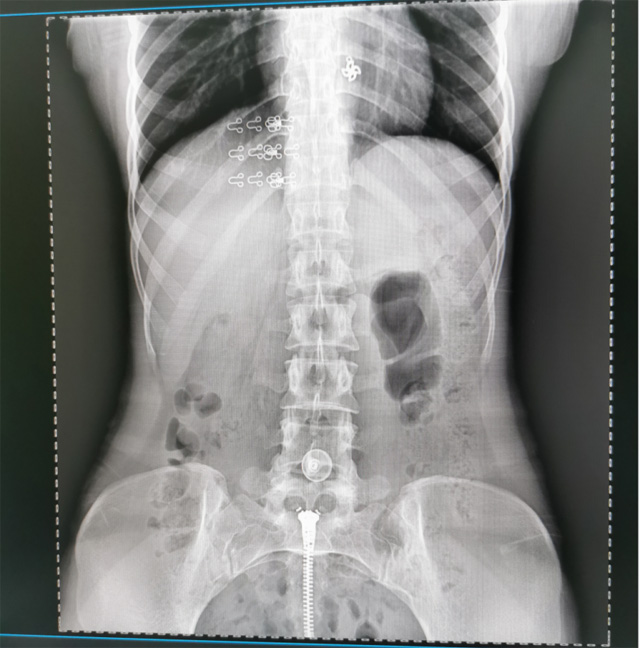

提高醫院的影像科的醫療服務水平,滿足滿足人民群眾不斷增長的醫療需求,促進醫療技術快速發展。醫院都引進懸吊DR拍片設備新一代數字化X線攝影係統。標誌著醫院的診療水平又上升一個新的台階。懸吊DR滿足人體頭部、胸部、腹部、腰椎、四肢等部位的數字攝影檢查,可以檢查呼吸係統疾病,心髒係統的疾病、骨關節係統的疾病,子宮輸卵管造影、胃腸道造影,.有職業病體檢篩查塵肺病功能。通過DR數字化攝影,分段連續、重疊采集數字化圖像,利用軟件對圖像進行拚接的方式來獲得全脊柱、全上肢或全下肢的圖像。新設備的圖像更清晰,臨床拍攝避免患者再次搬運和移動產生的痛苦,是創傷骨折患者的福音。輻射減少受照劑量50%,後處理能力強、圖像質量高。有效降低操作難度,縮短工作流程,尤其適合大批量體檢。

具有射線劑量小、圖像清晰度高、誤差小等特點,懸吊DR已廣泛應用於各級醫療機構的體檢中心,越來越受到臨床醫生的肯定和患者的青睞。為臨床診斷工作提供更加直觀有效的技術支持,大大提高了患者就醫效率從而為患者提供更加優質的醫療服務。提高了其成像質量和臨床應用價值,並極大減少了受照輻射劑量。有效滿足了各種常見疾病的臨床診斷和治療需求。以醫療質量為根本,以優質服務為導向,竭誠為人民群眾的健康保駕護航。